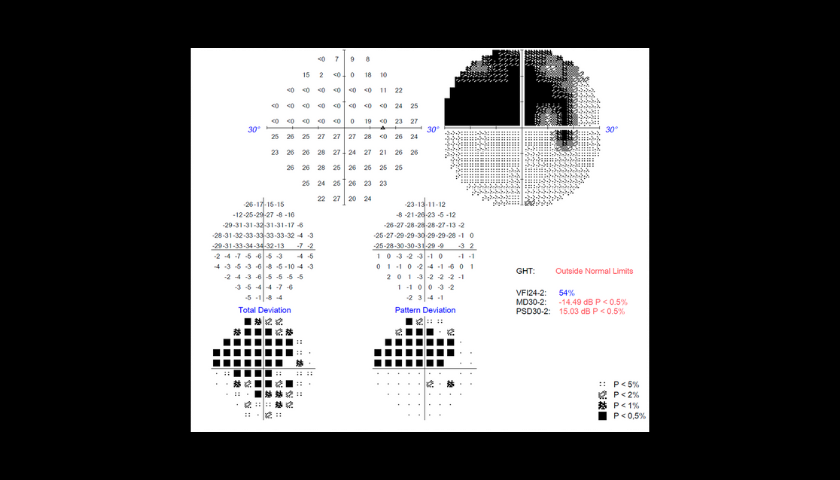

Os colírios são geralmente a primeira linha de tratamento. Pode ser necessário usar mais de um tipo de colírio em simultâneo. É crucial seguir o plano de tratamento porque a falta de uma dose diminuirá o efeito sobre a pressão intraocular, o que poderia levar a uma perda de visão. O doente será aconselhado a fazer controlos regulares para monitorizar a eficácia do tratamento. Durante a visita, o médico pode recomendar que o doente faça um exame OCT ou um Campo VISUAL (PEC) que irá avaliar o estágio da doença e a eficácia do tratamento.